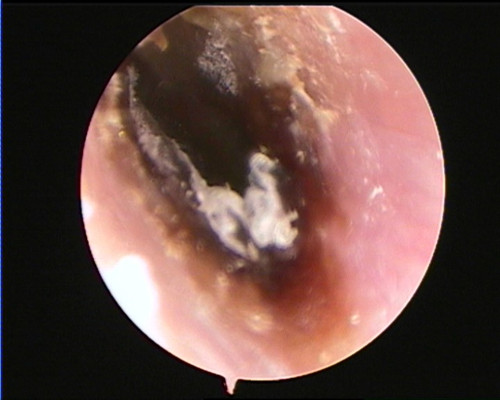

捷克论坛 耳鼻咽喉头颈外科三病区主任王宁通过耳内镜检查发现,吴女士左侧外耳道充血肿胀,耳道表面和鼓膜上还布满了大量真菌菌丝,吴女士被诊断为真菌性外耳道炎。